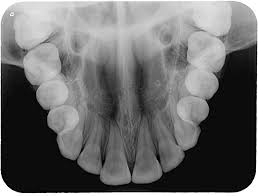

Las

imágenes radiográficas son esenciales para complementar el diagnóstico y tratamiento

a realizarse, son muy útiles para evaluar el crecimiento y desarrollo de los

maxilares, los estadios de erupción de las piezas denarias, las anomalías de

forma y tamaño, lesiones cariosas, los patrones de crecimiento cráneofacial,

lesiones traumáticas, fracturas, lesiones periapicales, tratamientos de

conducto. Mediante el análisis de las radiografías es posible evaluar aspectos

funcionales y patológicos desde temprana edad, lo que contribuye a dar un mejor

tratamiento preventivo incluso evitar complicaciones a futuro. Debemos recordar

que al paciente hay que tratarlo íntegramente como un todo y no solo quedarnos con los dientes.